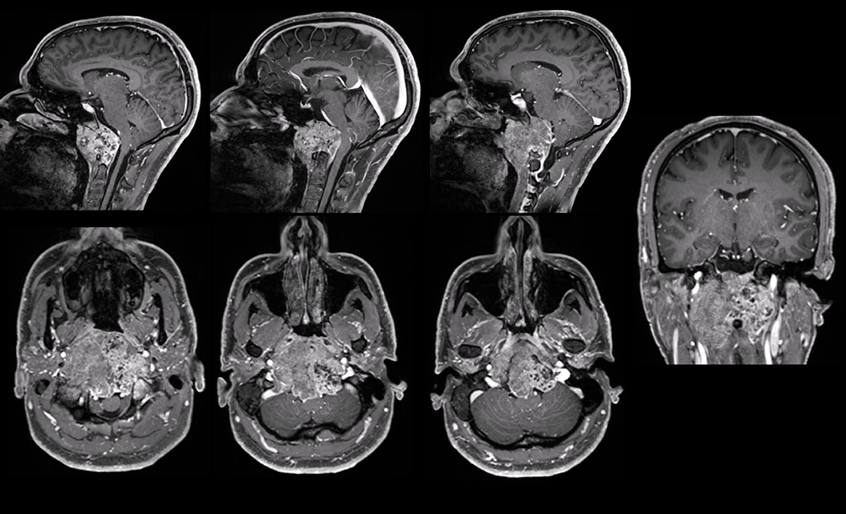

患者因"颈部疼痛"就诊,发现巨大脊索瘤,肿瘤直径达10厘米,体积96.5cm³,侵犯斜坡、枕骨髁、C1-C2椎体,严重压迫脑干。

治疗策略:采用经远外侧经髁入路进行显微镜+神经内镜双镜联合肿瘤切除,随后行枕颈融合术。创新性使用Roy-Camille技术进行固定,为后续质子治疗创造无金属通道。

结果:肿瘤完全切除,术后吞咽功能改善,颈部疼痛缓解。术后8周接受质子治疗,实现全面治疗。